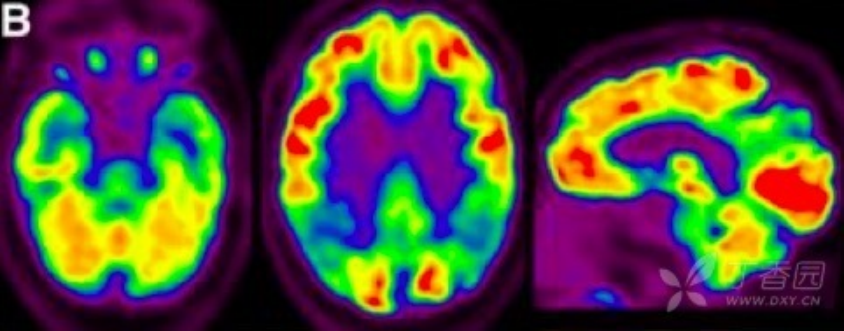

2.葡萄糖代谢 PET(FDG PET) FDG PET 用于测量神经元和胶质细胞的葡萄糖摄取情况,被认为是突触功能变化最敏感的指标。AD 患者可出现典型的颞顶区、后扣带回皮质和楔前叶葡萄糖代谢降低,具有 90% 敏感性以识别出 AD 与其他类型痴呆。也有研究发现,AD 早期颞叶出现高代谢,提示可能为疾病早期代偿表现。携带载脂蛋白 APOEε4 等位基因认知正常受试者也被发现与 AD 相似脑区的代谢异常。因此,作为衡量脑功能改变的指标,FDG PET 对 AD 疾病进展过程中脑功能改变的评估诊断价值更高。

图 3 AD 患者的 18F-FDG PET 成像